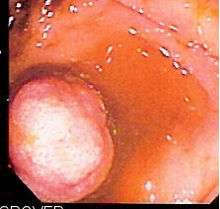

Screening for colorectal cancer, if done early enough, is preventive because almost all[20][21] colorectal cancers originate from benign growths called polyps, which can be located and removed during a colonoscopy (see colonic polypectomy).